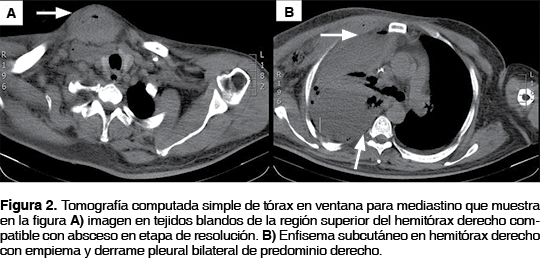

Se realizó tomografía computada simple de tórax que mostró datos imagenológicos de empiema y derrame pleural derecho con probable comunicación hacia región superior del hemitórax (figura 2). No pudo realizarse estudio contrastado por alto riesgo de nefropatía por contraste.

Bhatt et al., demostraron la utilidad de TAC en el diagnóstico de empiema necessitatis en un reporte de caso al mostrar la continuidad entre la pared torácica y espacio pleural.12 Radiológicamente, la TAC constituye un pilar fundamental en el diagnóstico, donde se aprecia una masa pleural de paredes gruesas, bien encapsulada asociada con una masa extrapleural en la pared torácica y que en la actualidad, se considera patognomónico de empiema necessitatis.10